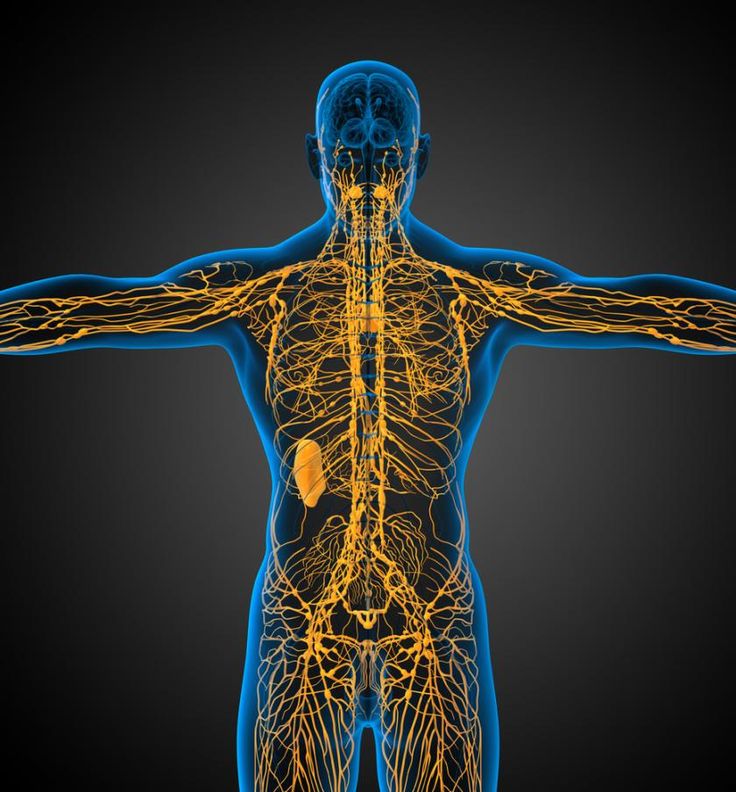

מוח ומערכת החיסון:

המערכת הלימפתית פועלת בין השאר, בהרחקת נוזלים בין-חלליים, ובהעברת תאי דם לבנים אל קשרי הלימפה. היא פועלת ברשת שבין הרקמות והאיברים שכוללים את השקדים, הטחול, הפוליפים והתימוס.

פרופ' קיפניס מהמחלקה למדעי העצבים של אוניברסיטת וירג'יניה פירסם שהמוח, כמו כל שאר הרקמות בגוף, קשור למערכת החיסון.

התגלית הזאת משנה לגמרי את הדרך שבה אנחנו תופשים איטראקציה נויר-אימוניות. החוקרים בטוחים עכשיו שבכל מחלה נוירולוגית שיש בה מרכיב חיסוני , יש תפקיד חשוב ואולי עיקרי לצינורות האלה.

הם טוענים שצינורות הלימפה היו מוחבאים היטב, והם עוקבים אחרי כלי דם גדול ההולך אל סינוסים ליד המוח.